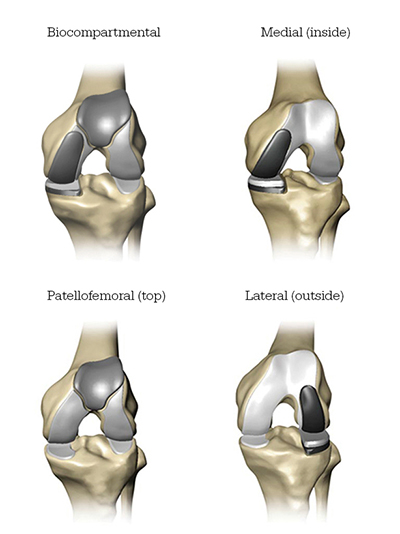

- Mako Robotic-Arm Assisted partial knee replacement is a treatment option for adults living with early to mid-stage osteoarthritis (OA) that has not yet progressed to all three compartments of the knee. Depending on where the arthritis affects the knee, patients may have an implant inserted in any of the following areas: